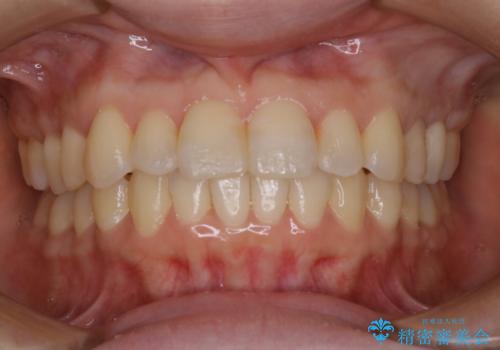

![[ インビザライン矯正 ] マウスピース矯正で治す、前歯のガタつきの症例 治療前](https://seimitsushinbi.jp/wp/wp-content/uploads/2022/02/324533f54aaa29eca08b0a9fdd3af7e2-500x350.jpg?v=1644473292)

![[ インビザライン矯正 ] マウスピース矯正で治す、前歯のガタつきの症例 治療後](https://seimitsushinbi.jp/wp/wp-content/uploads/2022/02/IMG_1698-500x350.jpg?v=1644473356)